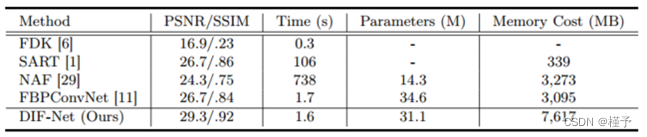

重建效率。如表2所示,FDK [6]需要的重建时间最少,但图像质量最差; SART [1]和NAF [29]需要大量时间进行优化或训练; FBPConvNet [11]可以更快地重建3D体积,但质量仍然有限。我们的DIF-Net可以在1.6秒内重建高质量的CT,比大多数比较方法快得多。此外,DIF-Net受益于强度场表示,具有更少的训练参数,需要更少的计算内存,从而实现高分辨率重建。

表2.不同方法在重建质量(PSNR/SSIM)、重建时间、参数和训练内存开销方面的比较。默认设置:10视图重建,输出分辨率为2563 ;训练批量为1。

†:由于内存限制,使用1283的输出分辨率进行评估。